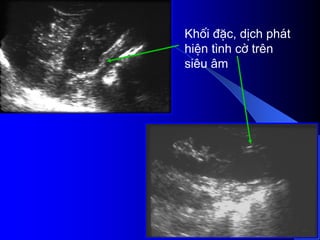

- Siãu ám phán biãût âæåüc khäúi âàûc vaì dëch.

Nãúu laì khäúi âàûc seî xem xeït cáúu truïc ám, coï thãø

giaím, âäöng hoàûc tàng ám, xem âäü âäöng nháút ám,

väi hoïa.

Nãúu laì khäúi dëch, seî tçm täø chæïc âàûc hoàûc vaïch

trong nang.

Siãu ám coï thãø tháúy haûch di càn, xám láún ténh

maûch.

Noïi chung khi phaït hiãûn khäúi âàûc trãn siãu ám,

cáön chuûp CLVT âãø âaïnh giaï roî hån baín cháút, sæû

xám láún, di càn.